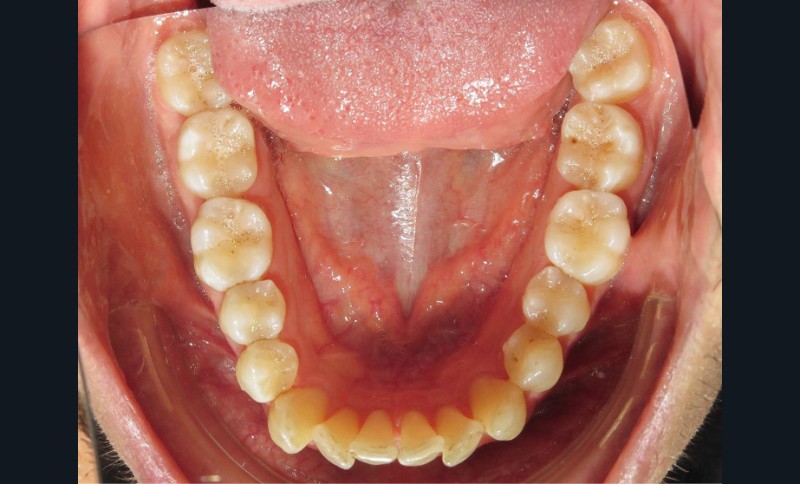

Diagnostic (fig. 1a-i)

Le patient consulte initialement pour des défauts d’alignement. L’examen clinique confirme l’existence d’un encombrement antérieur bimaxillaire, mais révèle aussi la présence d’une Classe II dentaire sévère, d’une exoclusion de la 27 et de troubles parodontaux (peu ou absence de papilles inter-dentaires). Sur le plan squelettique, le patient est relativement équilibré avec un profil harmonieux.